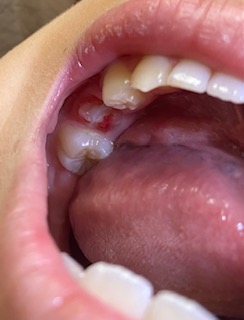

昨日最後の乳歯が抜けて、隣接していた6歳臼歯の近心側の歯茎のきわ辺りに白濁と一部分にごく小さく薄茶色の様な箇所がありました。

(目視では欠損などがあるかは分からず)。

写真を拝見した限りエナメル質に限定した軽い脱灰と着色のように見えます、それほど深刻ではないように思います、お菓子に気を付けてフロスを使う事で再石灰化すると思います。

現状、娘の白濁はかかりつけ医でエナメル質限局で欠損はなく(マイクロで確認していただきました)今は硬い状態との診断で、高濃度フッ素をぬってもらい次回また3ヶ月後の検診となりました。